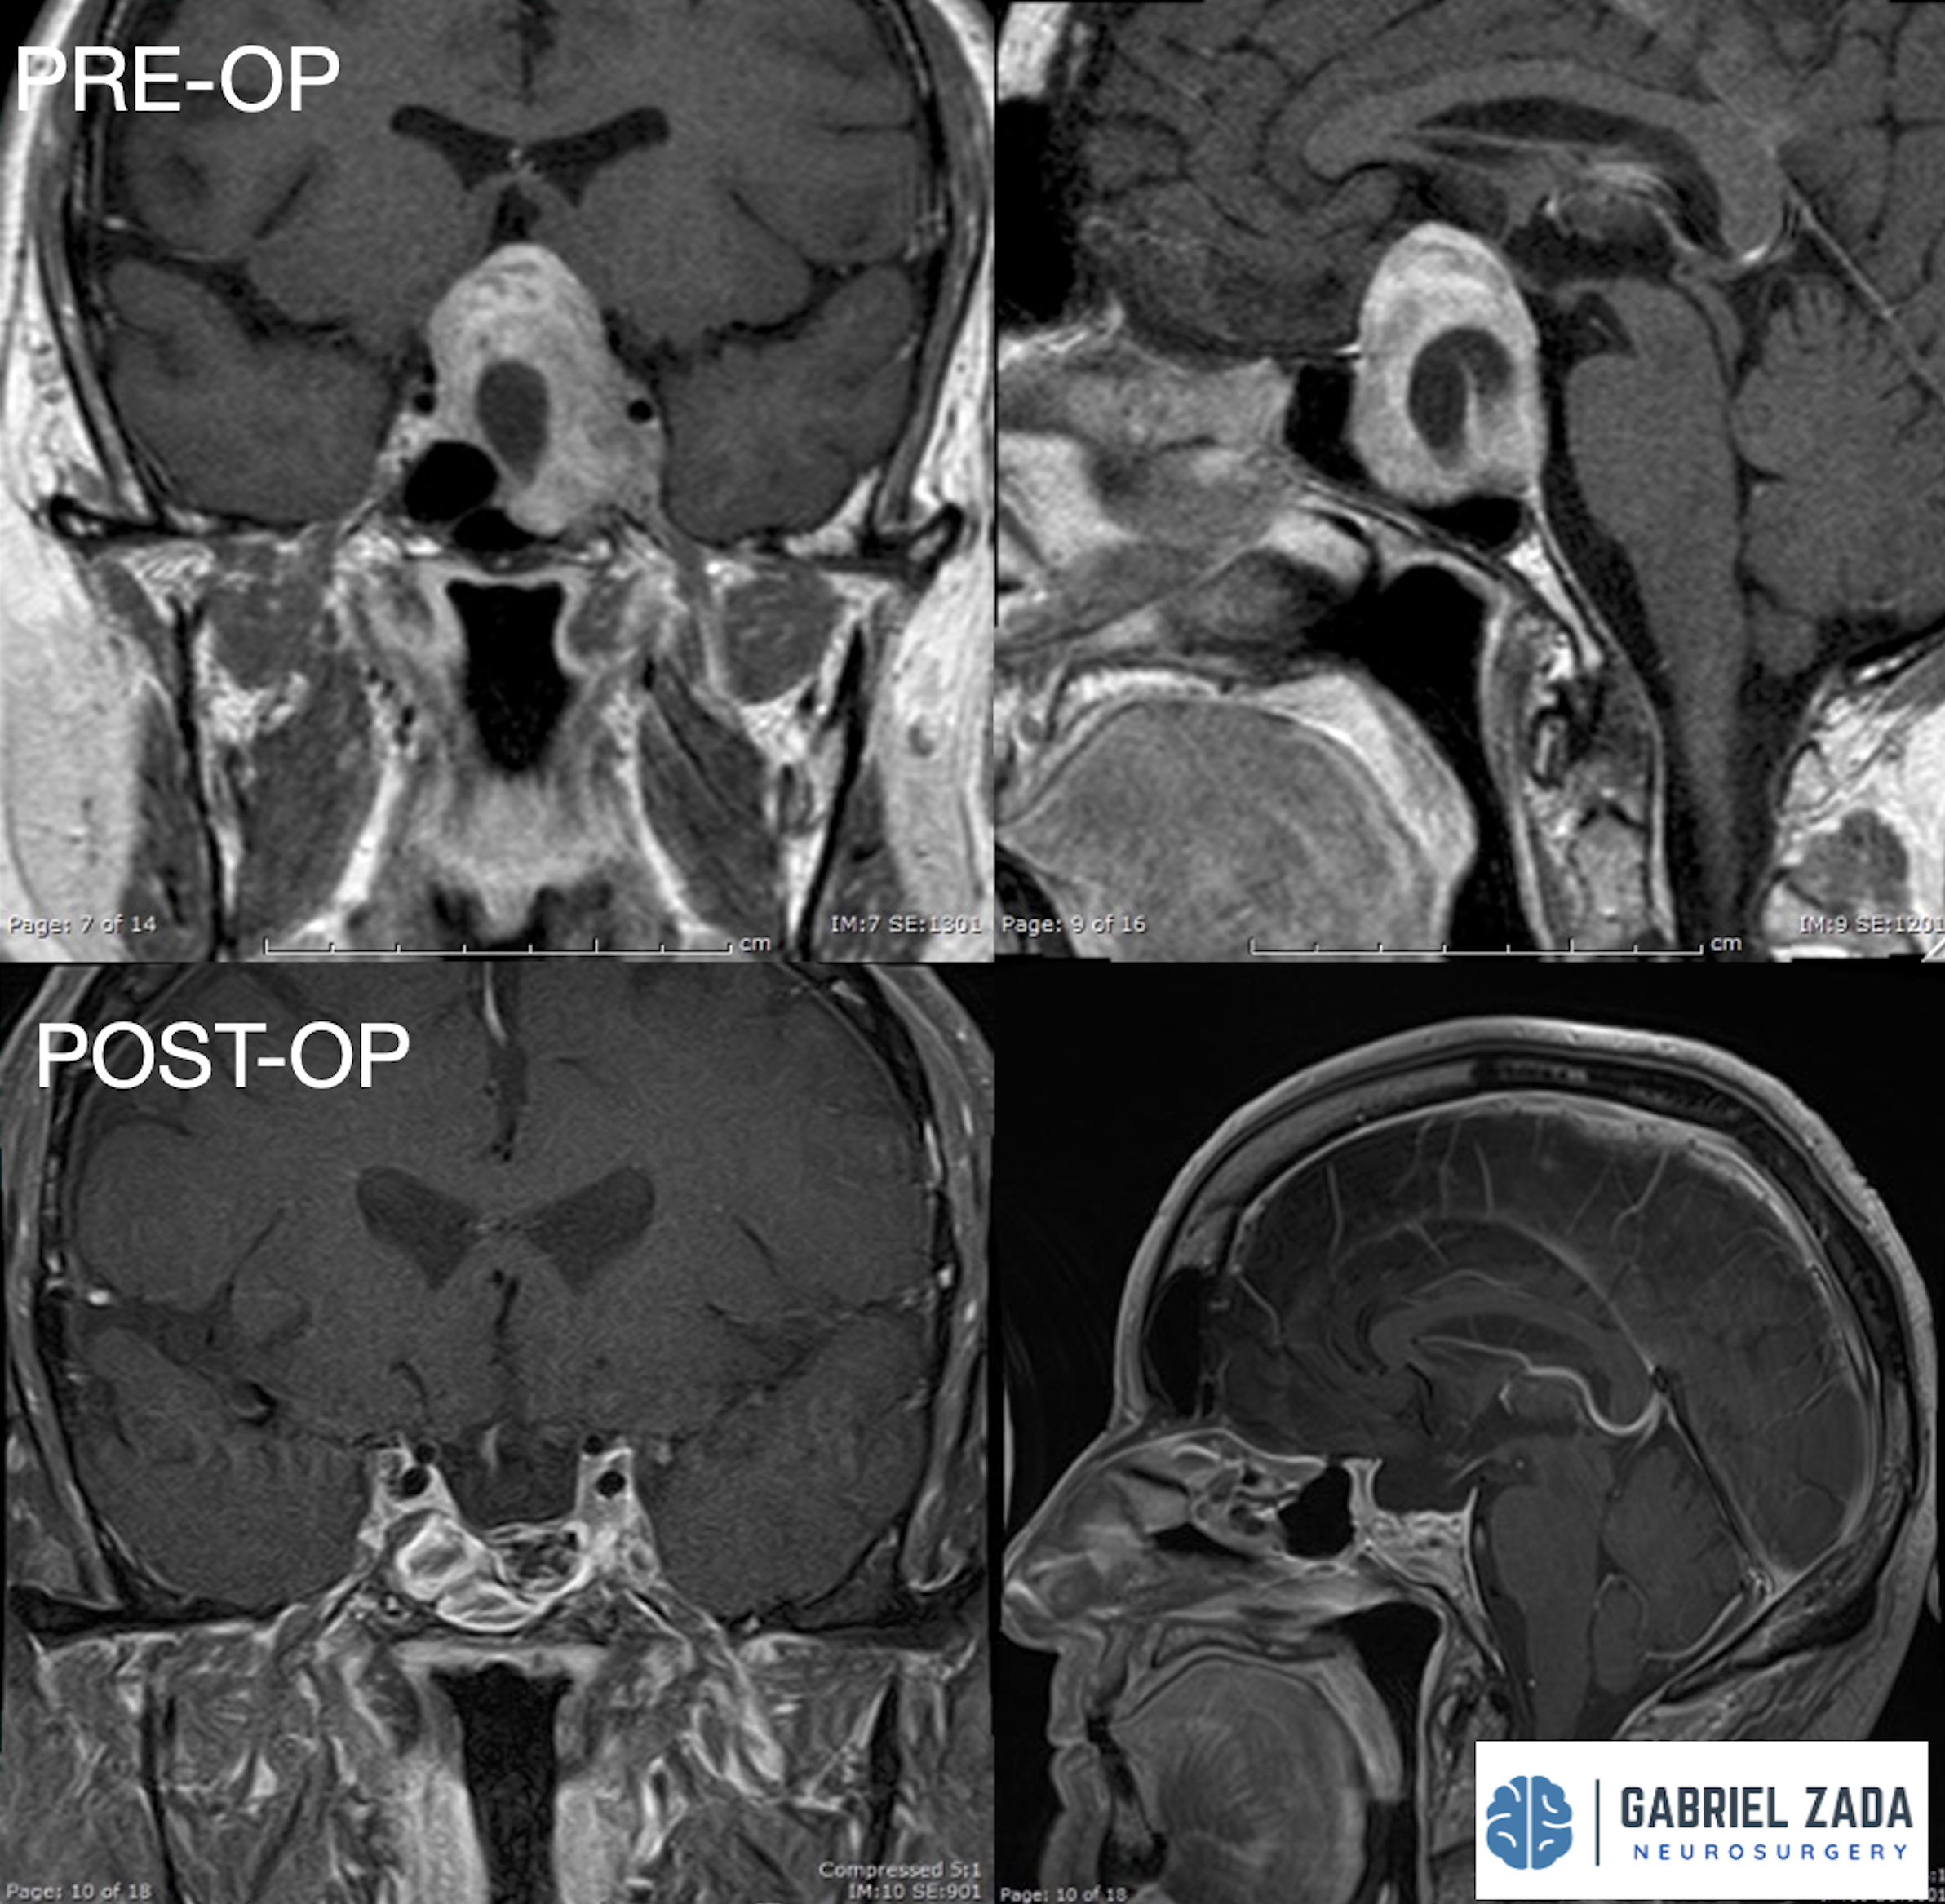

Explore this comprehensive gallery featuring pre‑ and post‑operative imaging of patients with skull‑base tumors treated by Gabriel Zada, MD, MS, FAANS, FACS. These cases highlight Dr. Zada’s expertise in advanced neurosurgical techniques and outcomes.

*Representative cases shown for educational purposes. All images de-identified. Individual results vary.